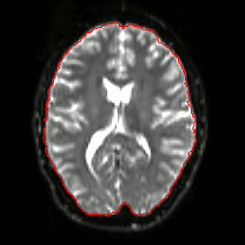

07 Masking

DWI

FA

SSE